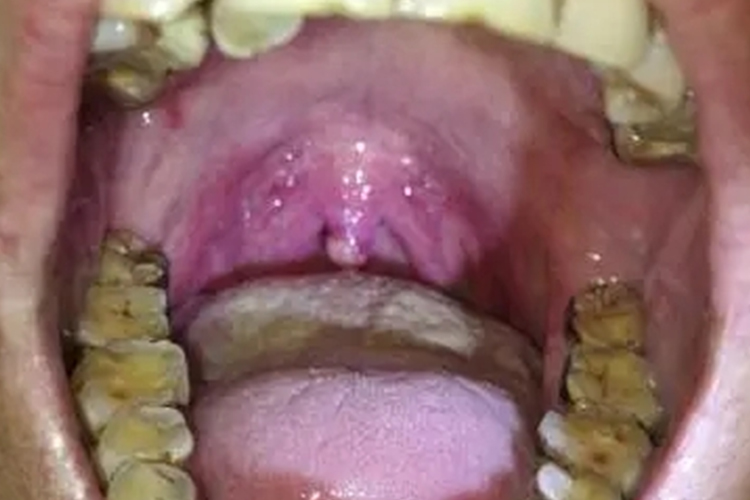

悬雍垂乳头状瘤主要表现为表面呈颗粒状,色白或淡红色,根部带蒂或较宽广。

悬雍垂乳头状瘤瘤体较小时多无自觉症状,常于体格检查或检查咽部其他疾病时,偶然发现。表面呈颗粒状,色白或淡红色,根部带蒂或较宽广。肿瘤较大时,可出现咽干、痒、异物感等,甚至可出现吞咽、呼吸及发声功能障碍。